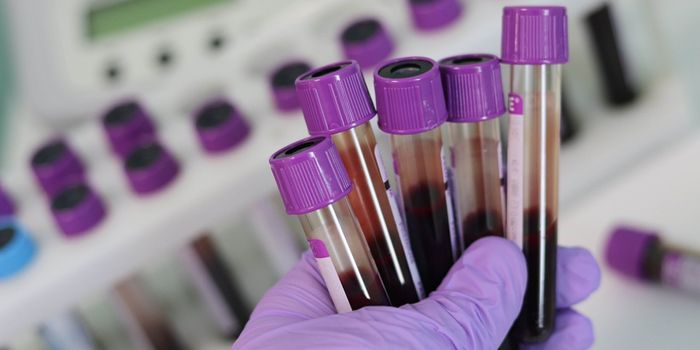

FEB 17, 2025Clinical & Molecular DXPreeclampsia is a complication that arises in 5-8% of pregnancies. It causes high blood pressure (hypertension) and may ...

JAN 19, 2025Clinical & Molecular DXWhen cancer is detected earlier, it can improve outcomes for patients. Liquid biopsies are one way to improve cancer det ...

DEC 27, 2024Clinical & Molecular DXClinicians may soon be able to use a fingerprint to determine whether a tuberculosis patient has taken the proper antibi ...